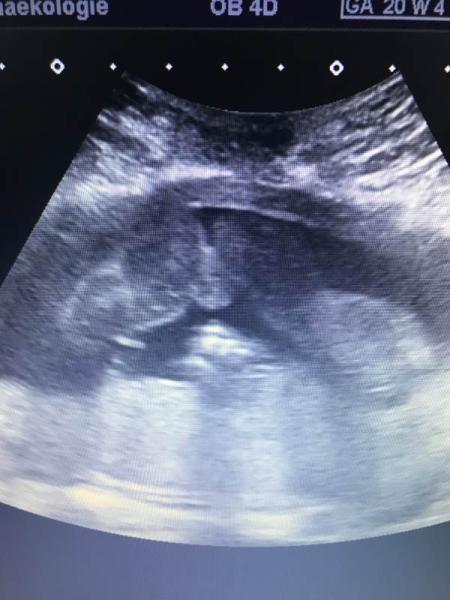

Hallo Ihr Lieben, ich hatte gestern mein 2.großes Ultraschall. Es ist zum Glück alles in Ordnung. Es ist alles dran, was dran sein sollte Mein Mann und ich sind beide sehr froh darüber. Wir hatten dann auch gestern unser Outing bekommen. Das letzte Mal vor 4 Wochen gab es ja nur eine wage Tendenz aber diesmal war sich die Ärztin sehr sicher. Ich habe euch mal das Bild angehängt. Vielleicht mögt Ihr erraten, was es wird? Wir freuen uns aufjedenfall beide sehr. GLG diddi

Bild zu 2.großes Ultraschall+Outing - Schwanger - wer noch? Rund um die Schwangerschaft

Richtig geraten, es wird ein Mädchen Wir freuen uns riesig und haben auch schon die ersten Babysachen gekauft. Ist ein tolles Gefühl nicht nur neutral zukaufen, sondern es darf auch ein bissl rosa und pink dabei sein Ich wünsche euch schonmal frohe Ostern